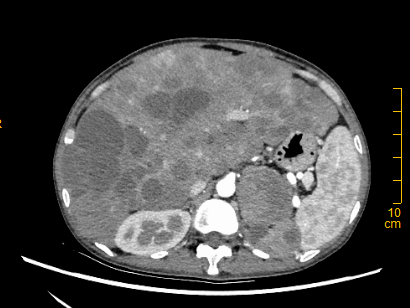

疗效也验证了医学的发展成果——接受规范化治疗3个月后,何女士腹胀、腹痛、体力低下、双下肢水肿等症状改善明显;5个月后,CT检查显示,肿瘤“强化程度较前减低,无强化区较前增大”,腹部从外部观察已与常人无异。

治疗5个月后,CT结果肿瘤“强化程度较前减低,无强化区较前增大”